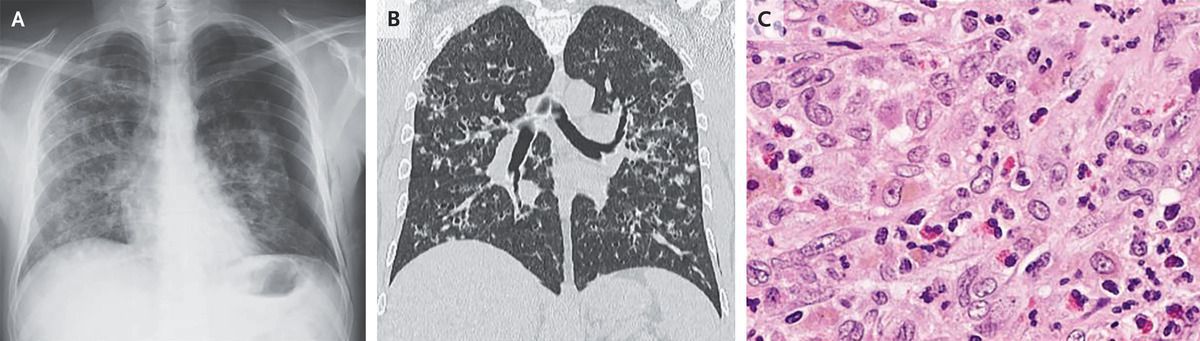

A 40-year-old man with a history of smoking presented to the emergency department with a 2-week history of cough, dyspnea, night sweats, and pleuritic chest pain on the left side. Physical examination was notable for decreased breath sounds over the left lung fields. A chest radiograph showed a large pneumothorax on the left side and interstitial infiltrates in both lungs (Panel A). The pneumothorax was treated with chest-tube thoracostomy. Subsequent computed tomography of the chest showed multiple cysts and nodules, predominantly in the upper and middle lung fields, with sparing of the costophrenic angles (Panel B). A transbronchial lung biopsy was performed. Histopathological tests showed a lymphocytic lung infiltrate with interalveolar septal thickening, eosinophils, and large cells with foamy cytoplasm and large nuclei (Panel C). Immunohistochemical staining was positive for S-100 protein, CD1a, placental acid phosphatase, and langerin. A diagnosis of pulmonary Langerhans-cell histiocytosis was made. Further testing revealed no evidence of systemic histiocytosis. BRAF testing was not done. The patient was advised to stop smoking, and a tapering dose of prednisone was prescribed. At the 6-month follow-up, the patient had ceased smoking; he was still taking low-dose prednisone, and his symptoms had abated.